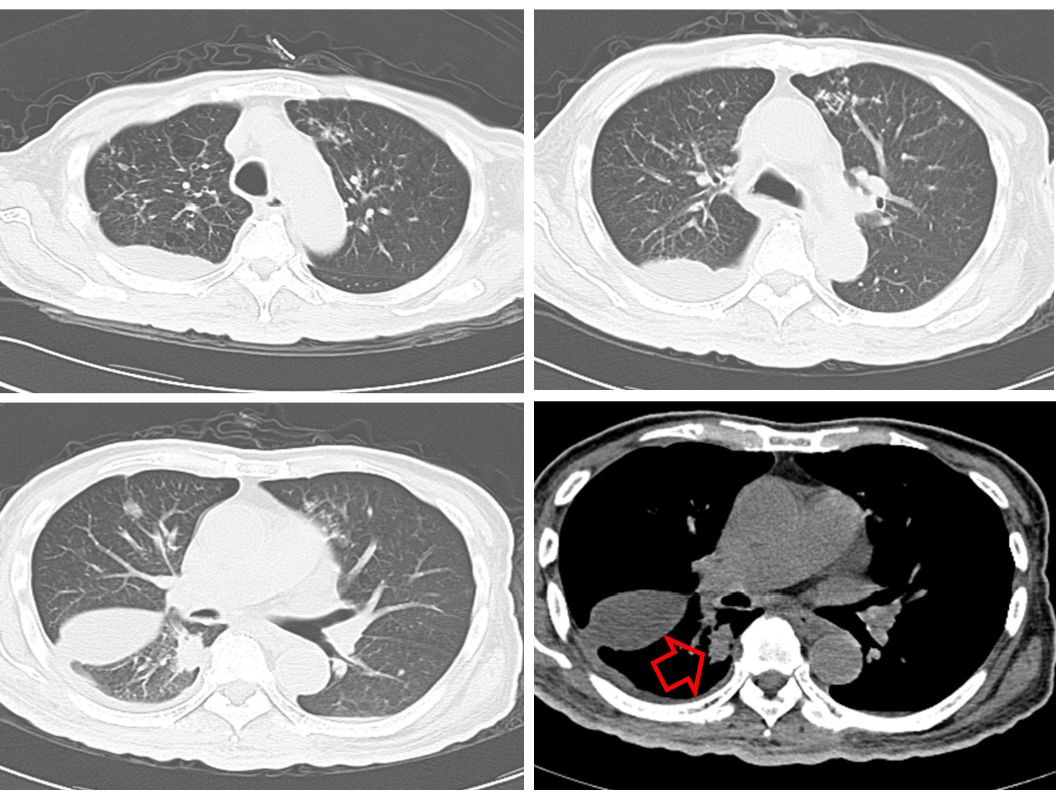

胸部CT(2020-03-03):左肺靶病灶直径59 mm,纵隔3、7区及双侧肺门淋巴结病灶直径20 mm(图1)。

图1:2020年3月3日,治疗前胸部CT

胸部CT(2020-04-18):左肺靶病灶直径59 mm,纵隔3、7区及双侧肺门淋巴结病灶直径20 mm(图2)。

图2:2020年4月18日,化疗2周期后胸部CT

胸部CT(2020-06-04):左肺靶病灶直径26 mm,纵隔3、7区及双侧肺门淋巴结病灶直径14 mm(图3)。

图3:2020年6月4日,替雷利珠单抗治疗2周期后胸部CT

本例患者为IIIB期左肺鳞状NSCLC,合并肺内、纵隔、及双侧肺门淋巴结转移,驱动基因阴性,PD-L1未检测。经第一阶段化疗治疗,疗效评价为SD,病情平稳但无明显缓解。予以第二阶段替雷利珠单抗联合化疗治疗2个周期后,病灶直径明显缩小,疗效评价达到PR。患者经替雷利珠单抗联合化疗治疗4周期后疗效评价仍为PR,病情平稳,治疗过程中出现的不良反应仅为皮疹,经对症治疗后缓解,安全性良好。